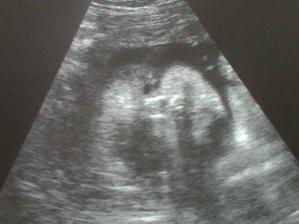

Vydržela to tajit tatínkovi až do 22/10 kdy jí pan doktor potvrdil, že je všechno v pořádku. V ordinaci se i rozplakala, no jo to jsou asi ty hormony, které jí teď kvůli mě pracují. Dostala i mojí fotečku, zatím tam nejsem žádný fešácký miminko ale určitě porostu do krásy 🙂).

9/12 proběhla screening v 11+5 - výsledky dopadly výborně a asi budu holčička. Skoro celou kontrolu jsem prospinkala, ale nakonec mě paní doktorka vzbudila tak jsem jim ukázala jak umím pracovat s ručičkama a nožičkama. Mamince zase ukápla slzička

8/1 provedeny testy v 16. týdnu - pan doktor, říkal, že když dopadly ty v 12tt dobře tak toto musí taky. Další poradna kde bude i ultrazvuk mamku čeká 29.1. Už se snad ukáže na 100% co budu zač 🙂 29/1 kontrola + UTZ - brouček byl natočen z profilu, takže zatím stále nevíme. Ale věříme výsledkům z genetiky, že to bude holčička. 3.2 maminka začala poprvé citím pohyby. Zatím to byly lehké kopanečky ale počkejte, až naberu sílu 🙂 13/2 kontrola srdíčka - vše v pořádku, všechno na svém místě 🙂) 19/2 kontrola na genetice. Vše je skvělé, naše pusinka je v pořádku akorát je hrozně lenivá. Byli jsme zvědaví na 4D fotky obličejíčku, ale ona je tvrdohlavá zřejmě po tatínkovi a tak se nechtěla ani po 2 hodinách čekání v čekárně ukázat. Takže máme fotečku pouze ouška a jejího posedu. Budeme si muset na to, jak vypadá počkat ještě nějaký pátek. Tak tatínek taky začal cítit ty brutální kopanečky, které musí maminka trpět 🙂) 15.4 kontrola u pana doktora, maminka dostala železo, podle výsledků krve ho má málo. A konečně jsem se ukázala obličejíčkem, takže dostala mojí fotečku. Škoda že jsem se nenatočila když jsem byla na 3D ultrazvuku, ale i tak jde vidět, že budu krasavice30.4 nástup na mateřskou dovolenou, 32 tt a 8 kg navíc.18.5 kontrola u pana primáře Nevrly, zkontroloval nás ultrazvukem. Lili je drobounká a bude mít pod 3,5 kg a také máme méně plodové vody tak proto máme malé bříško, což si ale maminka nemyslí 🙂 máme navíc skoro 10 kg, snad už to moc neposkočí 17.6.2009 tak máme poslední týden do termínu porodu, snad si Lilinka řekne sama kdy chce přijít na svět aby nám ten porod nemuseli vyvolávat. Maminka si užívá poslední chvíle těhotenství. Přibrala 12 kg a v těch vedrech co teď jsou jí krásně natékají nohy. Moooc si to "užívá" 🙂